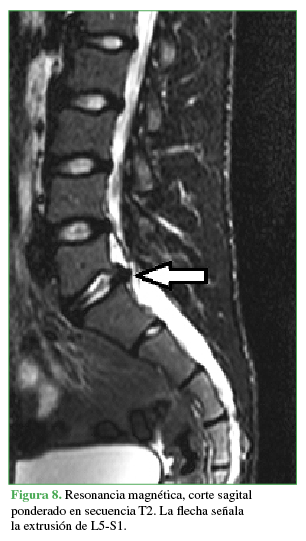

Las distintas patologías informadas se muestran en la Tabla 6 y las Figuras 6,7,8,9,10,11 y 12.

La flecha señala la extrusión de L5